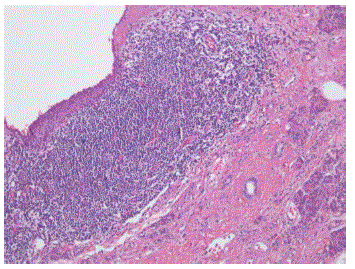

Figure 5. Histopathological findings of the cyst: stratified squamous epithelium with adjacent lymphoid infiltrate, without signs of atypia